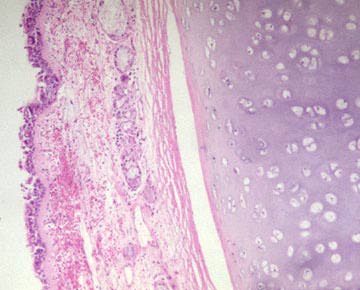

Microscopic section of normal bronchus showing respiratory epithelium, submucosal glands and cartilage.